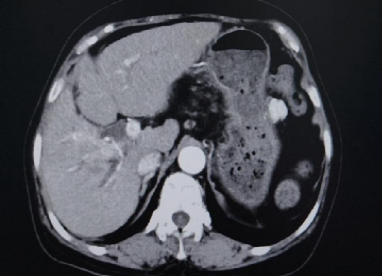

CT(2025.2.18):1、肝右叶异常强化团块影伴周围胆管扩张,考虑肝内胆管癌可能性大,门静脉右支充盈缺损影,考虑癌栓形成。2、脾脏缺如;胆囊、胰腺、双肾及双侧肾上腺未见明显异常

超声提示:肝内低回声区,考虑肝右叶胆管Ca,门静脉右支Ca栓形成

入院诊断:1.肝内胆管癌伴门静脉右支癌栓;2.病毒性肝炎慢性乙型;3.肝炎后肝硬化。

与2025-02-18日腹部增强片对比示:1.肝右叶多发低密度结节,考虑胆管癌,最大病变内多发颗粒状致密影,考虑介入术后改变,较前病变内坏死增多。肝中静脉局部走行于病灶边缘,管腔未见明显受侵。2.门脉右支起始处少许癌栓,远端未见显影,考虑治疗后改变。3.脾脏缺如;胆囊继发性改变,胆囊窝积液。肠系膜间可见多发稍大淋巴结。